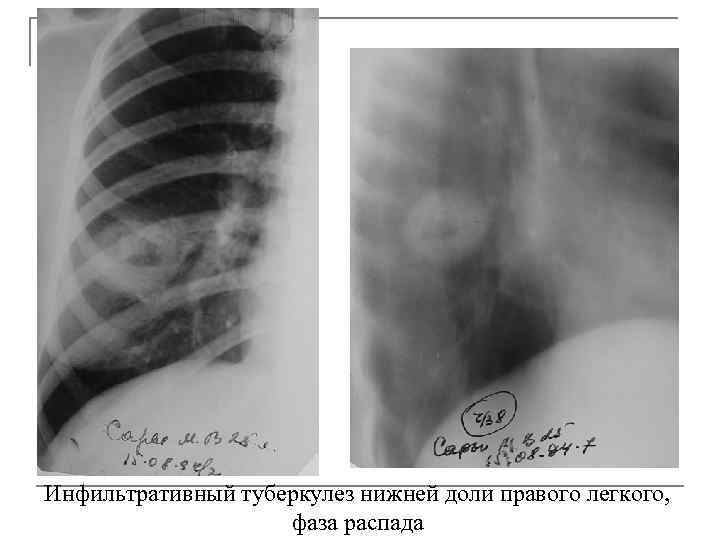

Иллюстрации по теме очагового и инфильтративного туберкулеза